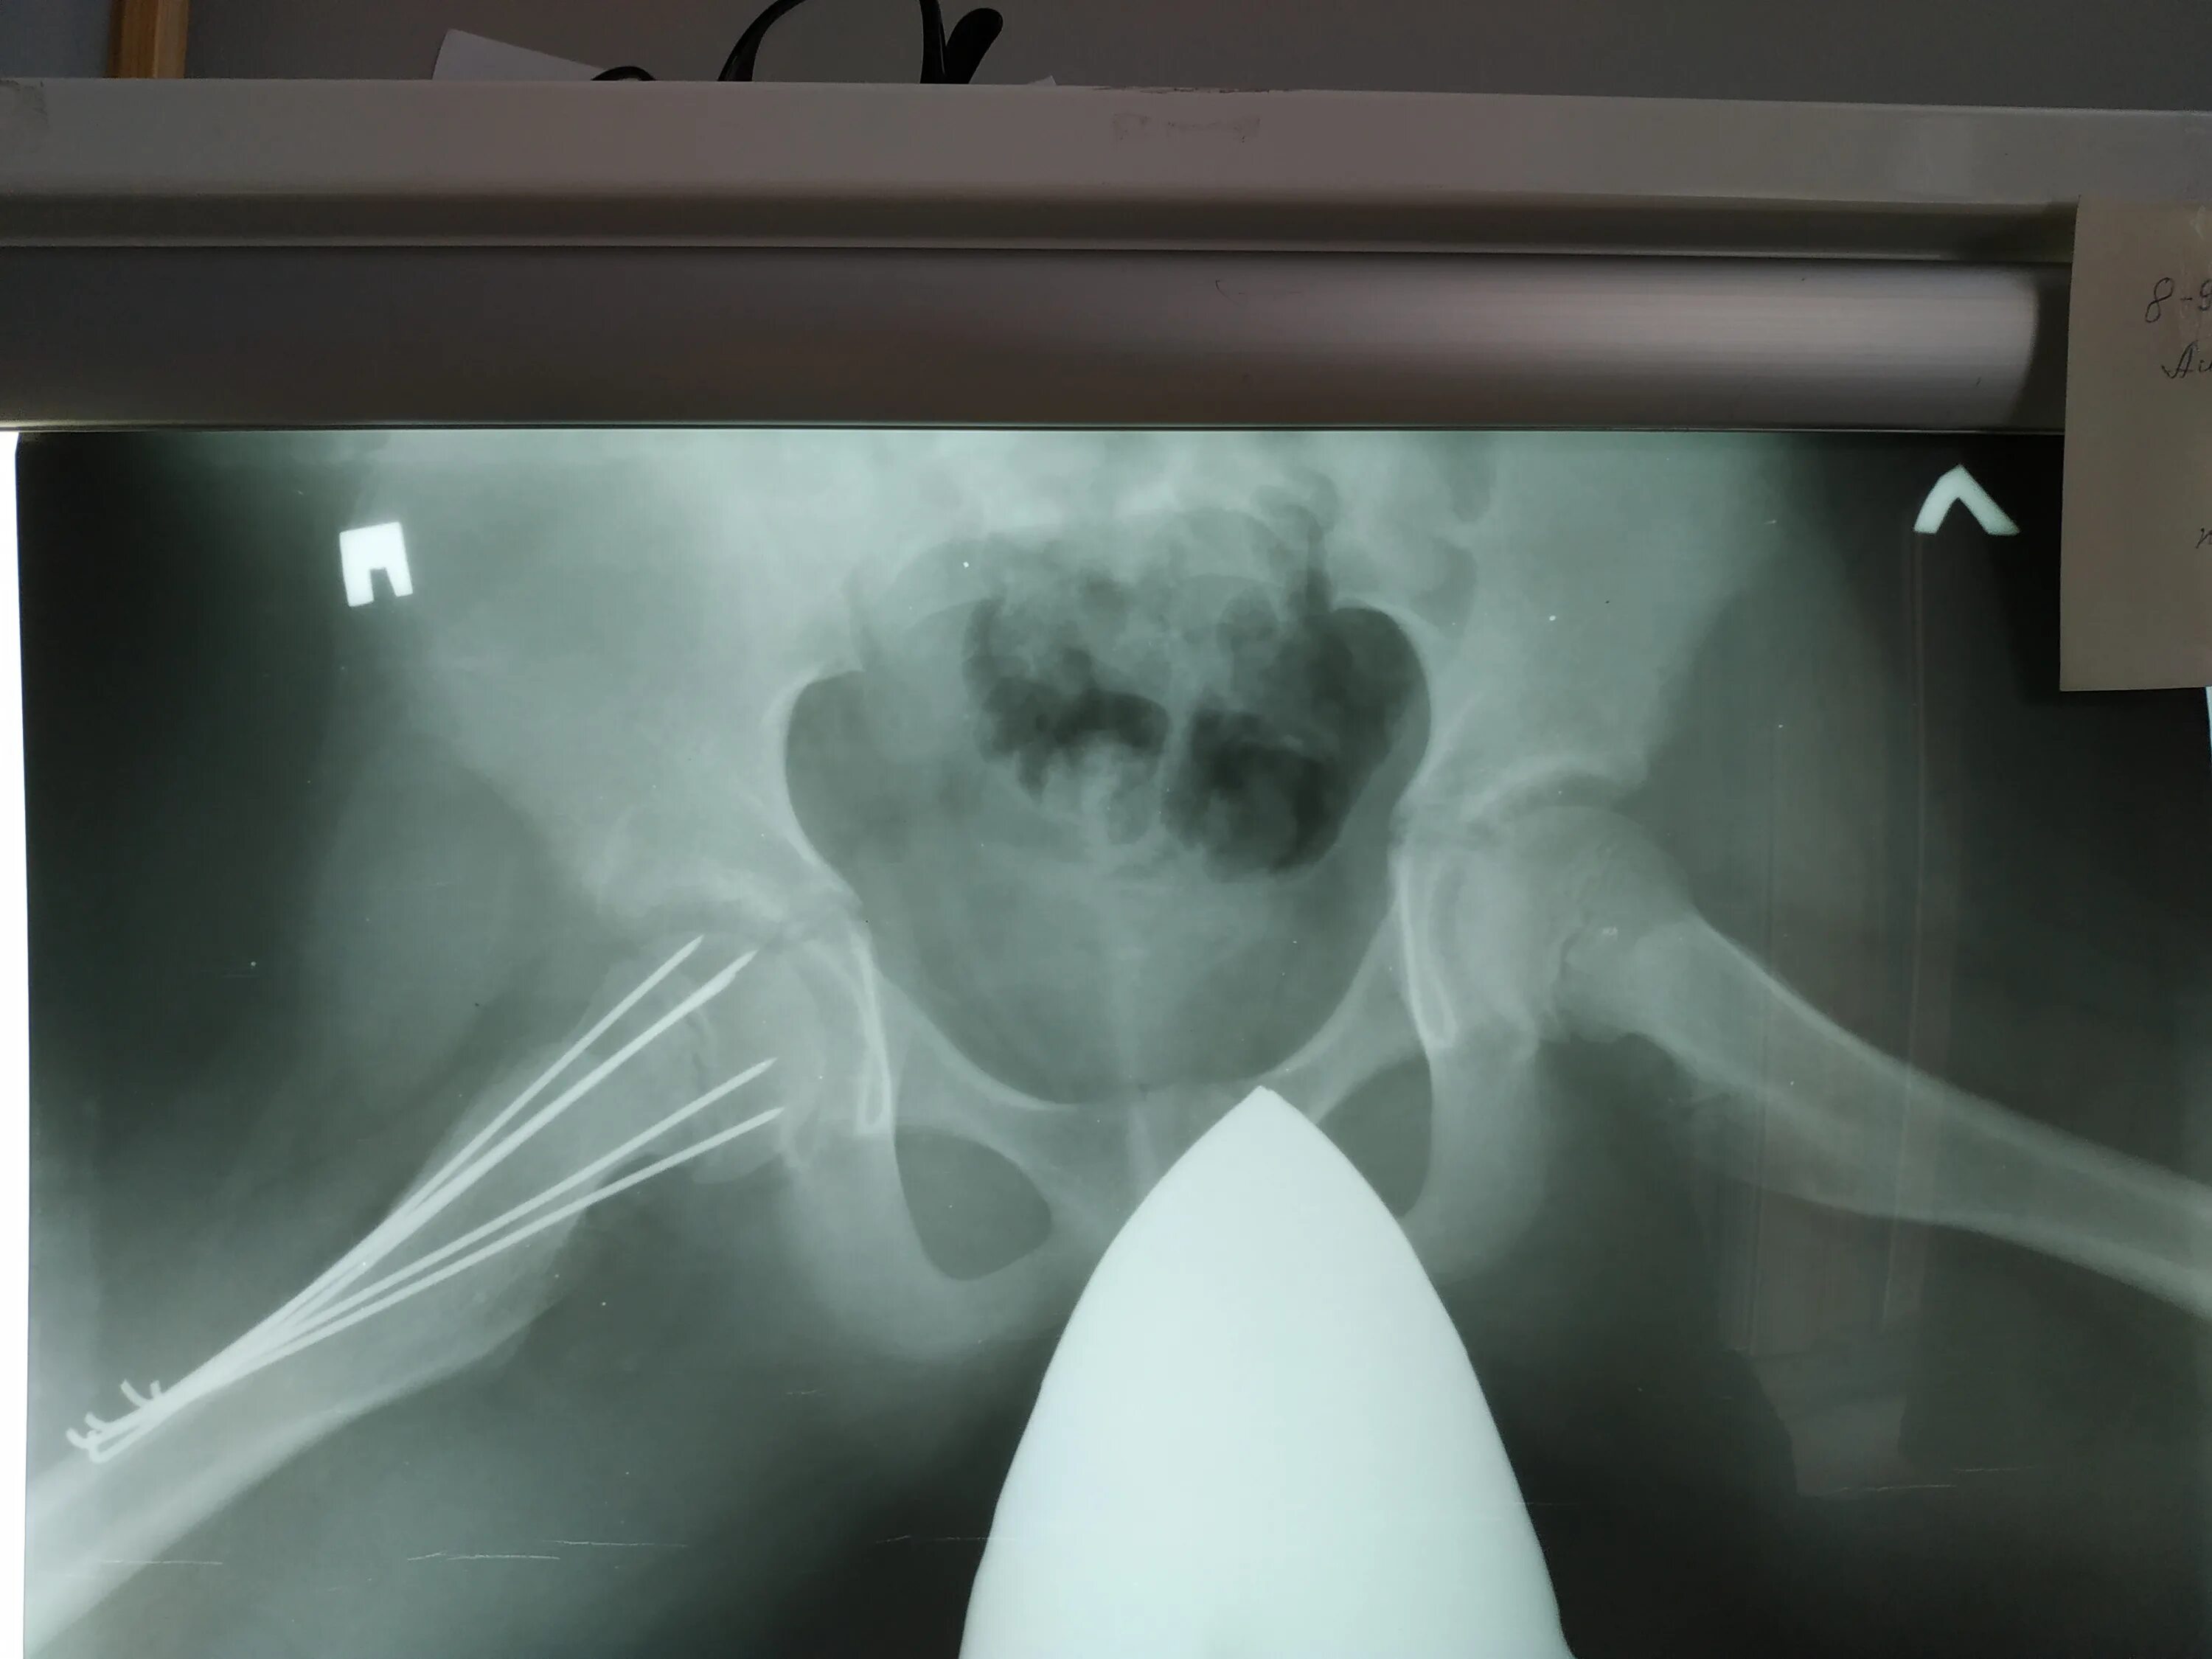

Проекции рентгена тазобедренного сустава